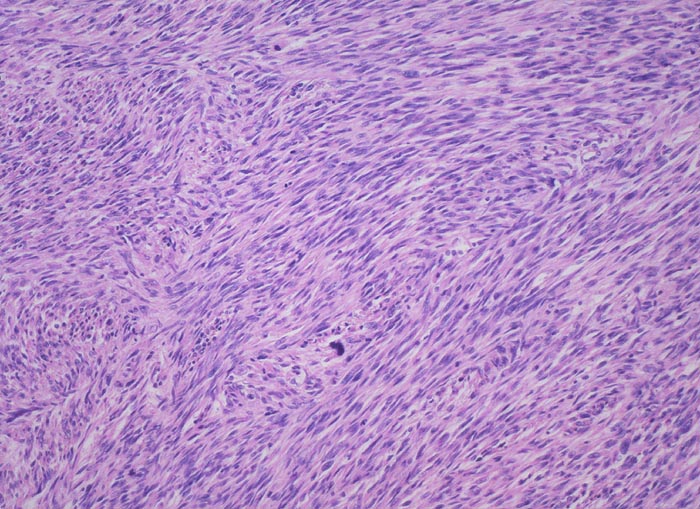

Morphologische Merkmale:

• Tumordurchmesser meist mehr als 10cm.

• Stellenweise unscharfe Begrenzung des Sarkoms zum nicht neoplastischen Myometrium (Fragment oben rechts).

• Die spindeligen Tumorzellen mit längsovalen Kernen und reichlich kräftig eosinophilem Zytoplasma bilden Faszikel ähnlich wie nicht neoplastische glatte Muskulatur.

• Alle drei histologischen Malignitätskriterien sind erfüllt:

• Tumornekrosen.

• Bereits in der Übersicht (10x) erkennbare diffuse signifikante Zellatypien.

• Vermehrt Mitosen: mehr als 10 Mitosen / 10 HPF (40x). Das sollte der Kliniker dem Pathologen mitteilen: